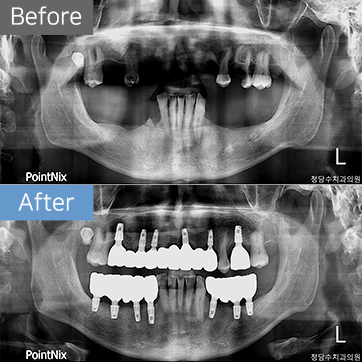

임플란트 40대남 임플란트

40대남 임플란트